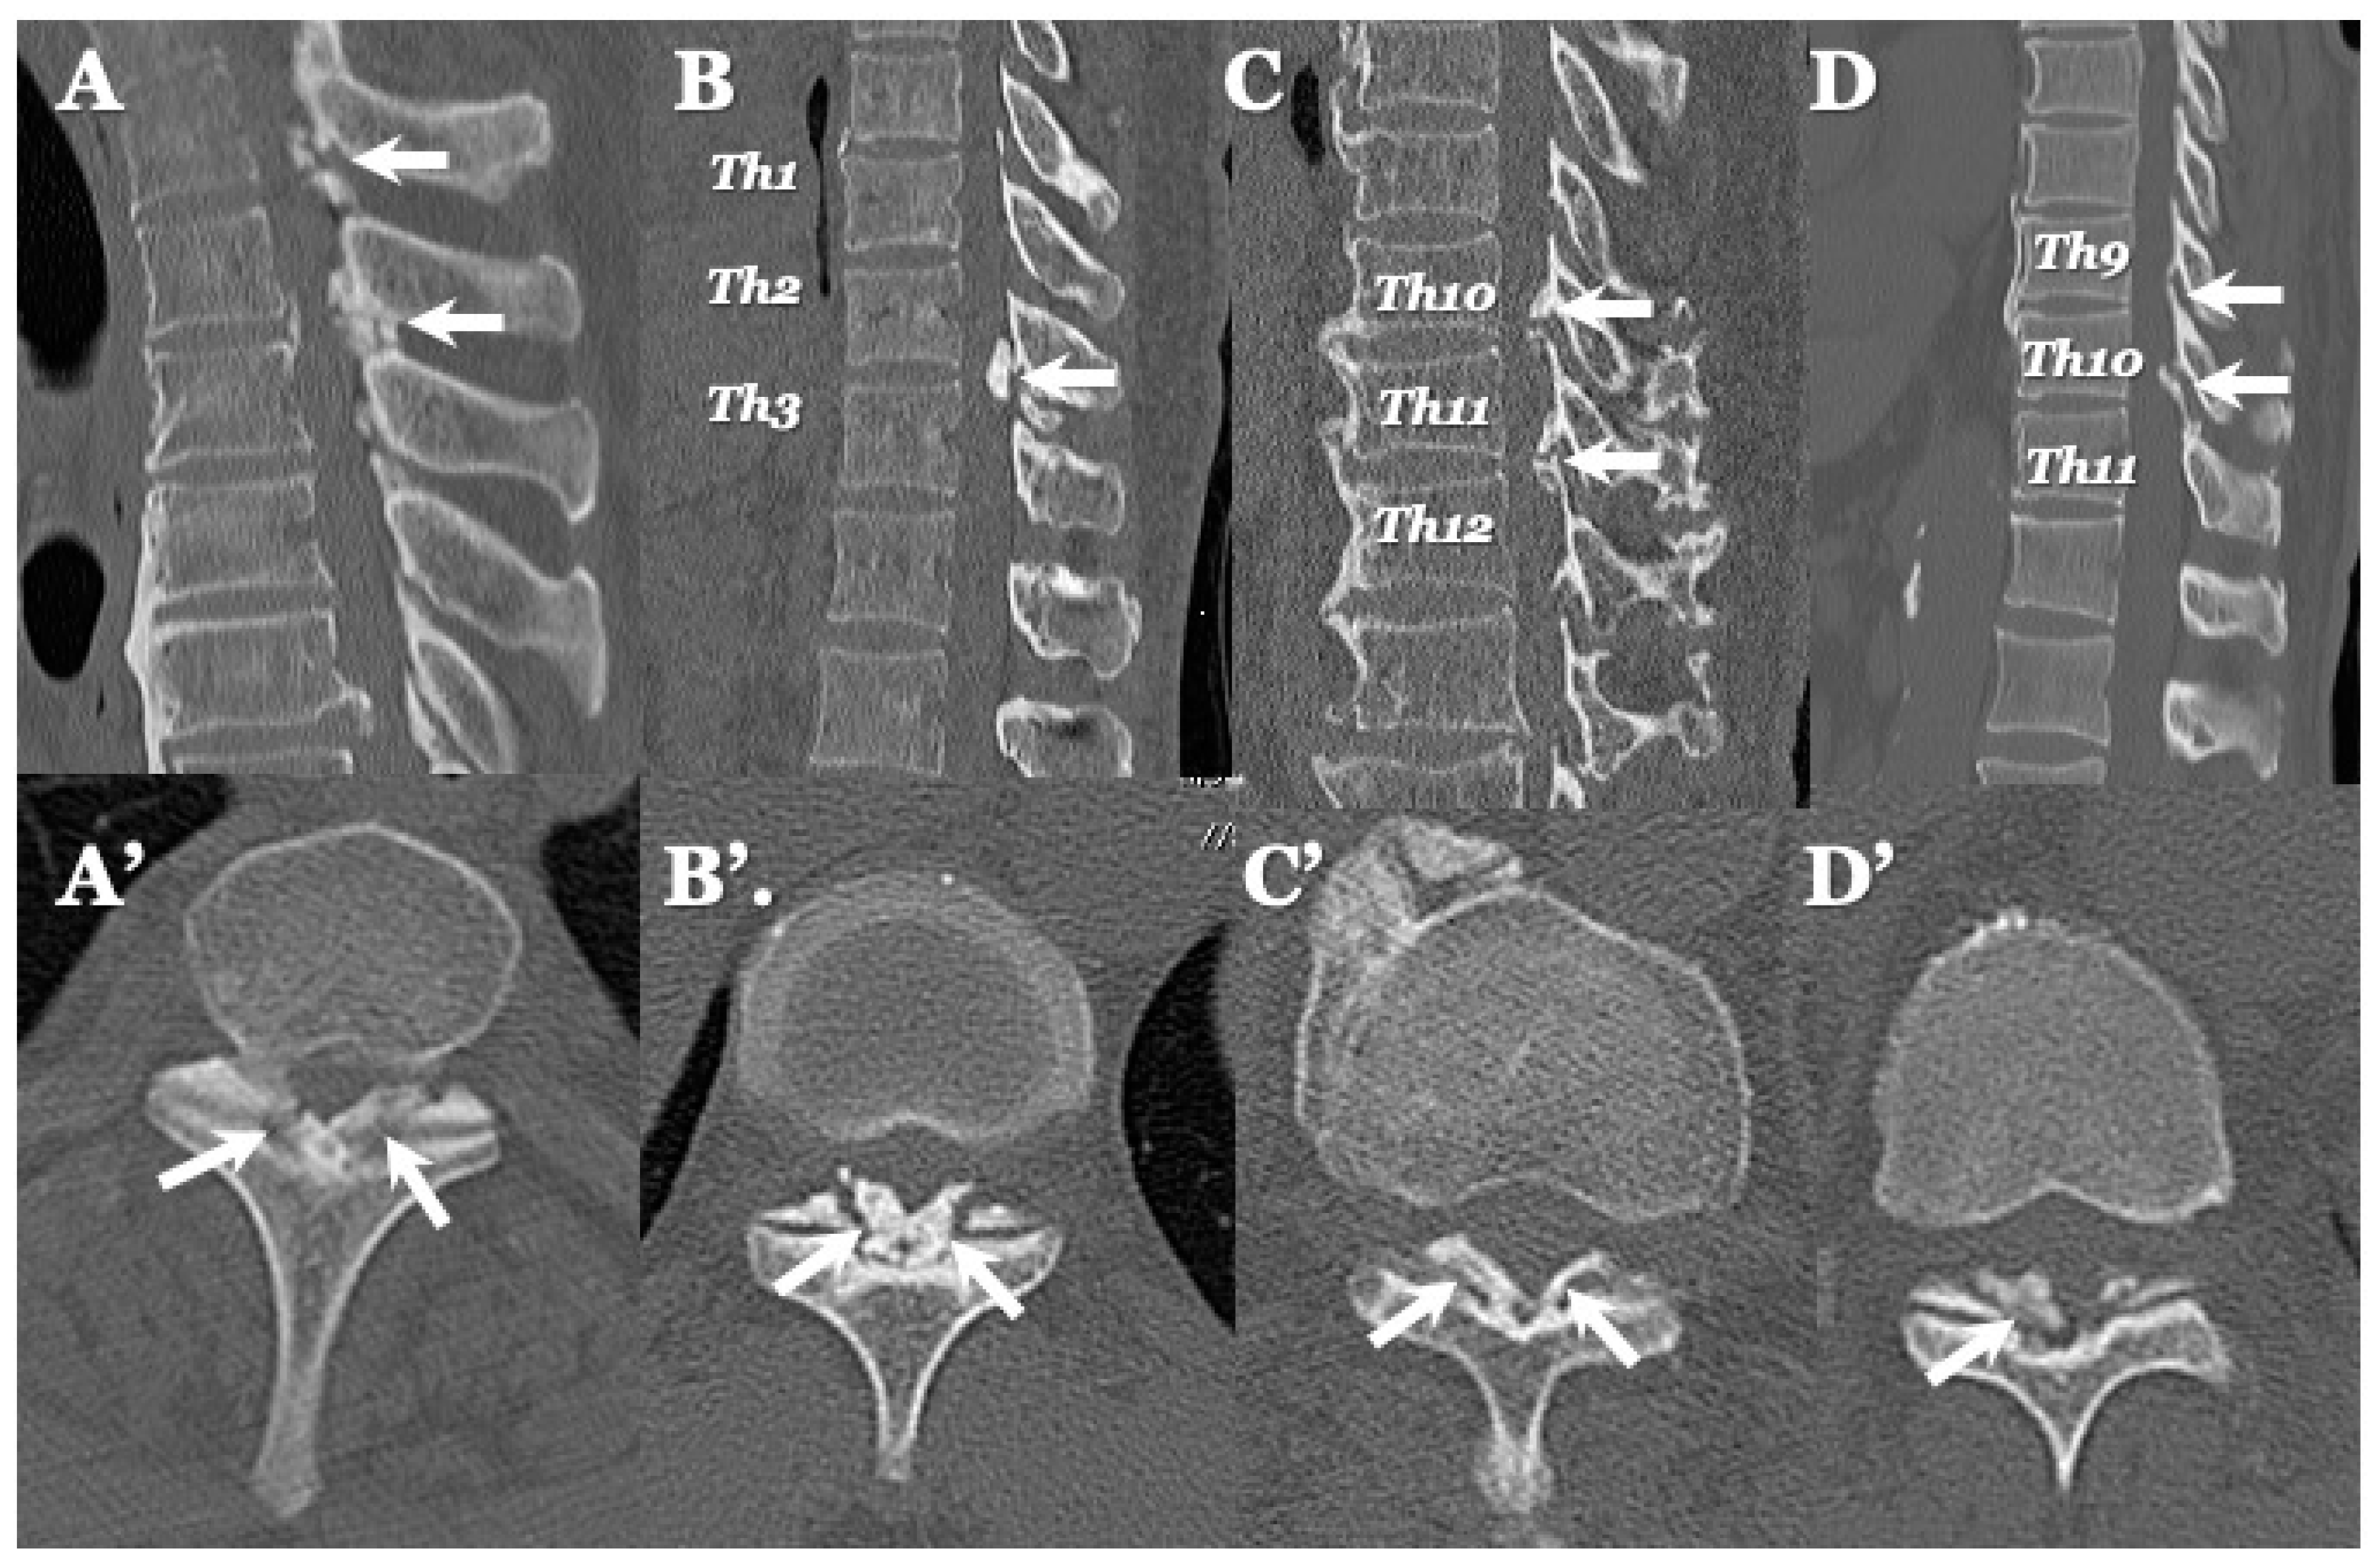

3.3. Neuroradiological Findings (Figure 3, Figure 4, Figure 5 and Figure 6; Table 3)

CLF: All cases exhibited spondylotic changes. Developmental narrowing (anterior-posterior diameter of spinal canal < 12 mm) of the spinal canal was observed in five cases, disc herniation in four cases, and ossification of the longitudinal ligament in three cases. Two-dimensional (2D)-reconstructed CT images demonstrated “multiple islands of speck-like and egg-shaped” high-density mass, “diffuse and speck-like” high-density masses, and/or “egg-shaped” high-density masses in the ligamentum flavum (Figure 3). In three cases, there was ossification of the longitudinal ligament (Table 3). MR T2-weighted images showed these mass lesions as areas of low intensity or isointensity, with compression of the spinal cord. The presence of both low-intensity and isointense regions suggested a combination of calcification and ligamentum tissue (Figure 4). In five cases, dynamic X-rays of the cervical spine demonstrated instability of joints (Table 3).

Figure 3.

Two-dimensional CT images of CLF. Two-dimensionally reconstructed CT scan axial image (A) and sagittal image (A’) CT scan demonstrating “egg shape” high-density mass contacting with laminae (arrows) and posterior osteo-spur at the C5/6 intervertebral level (black arrows). Two-dimensionally reconstructed CT scan axial image (B) and sagittal image (B’) demonstrating “diffuse and speck like” high-density mass contacting with laminae in ligamentum flavum (white arrows). Two-dimensionally reconstructed CT scan axial image (C) and sagittal image (C’) demonstrating “egg shape” high-density mass in ligamentum flavum on the left side in (C) and along the ligamentum flavum in (C’) (white arrows), ossification of posterior longitudinal ligament at the C4/5, 5/6 (white arrowheads), and listhesis at C3/4 intervertebral level. Two-dimensionally reconstructed CT scan axial image (D) and sagittal image (D’) demonstrating “multiple islands of speck like and egg shape” high-density mass in ligamentum flavum (arrows) and ossification of longitudinal ligament at C3/4 (white arrowhead).

OLF: There were spondylotic changes in 17 cases, developmental narrowing of the spinal canal in 7 cases, disc herniation in 7 cases, ossification of the longitudinal ligament in 4 cases, diffuse idiopathic skeletal hyperostosis (DISH) in 4 cases, and ankylotic spinal hyperostosis (ASH) in 3 cases [31,51,52]. Two-dimensionally reconstructed CT images showed beak-like ossification extending into the intervertebral foramen (Figure 5) (Table 3). MR T1-weighted and T2-weighted images demonstrated low-intensity masses in the dorsal spinal canal, which compressed the spinal cord. In some cases, there were high-intensity spots, suggesting the formation of bone marrow (Figure 6). In three cases, dynamic X-rays of thoraco-lumbar spine demonstrated joint instability (Table 3).

Figure 5.

Two-dimensional CT images of OLF. Two-dimensionally reconstructed CT scan sagittal images (A–D) image and axial image (A’–D’) showing beak-like ossification extended to intervertebral foramen (white arrows).

4.2. Comparison of Neuroradiological Findings between CLF and OLF (Figure 3, Figure 4, Figure 5 and Figure 6; Table 3)

CLF: A two-dimensionally reconstructed CT scan revealed “multiple islands of speck-like and egg-shaped” high-density mass and/or “diffuse and speck-like” high-density mass within the ligamentum flavum. MR T1- and T2-weighted images depicted these mass lesions as low intensity or isointense, with compression of the spinal cord. The presence of low-intensity and isointense regions suggested a combination of calcified regions and ligamentum tissue (Table 3, Figure 1 and Figure 2) [3,4,6,7,9,10,12,14,15,17].

OLF: Two-dimensionally reconstructed CT scan images showed beak-like ossification extending into the intervertebral foramen. MR T1-weighted and T2-weighted images demonstrated a low-intensity mass within the dorsal spinal canal compressing the spinal cord. In some cases, the presence of high-intensity spots suggested bone marrow formation (Figure 3 and Figure 4) [18,26,29,30,31]. In some cases, OLF was associated with DISH and ASH, indicating a more generalized ossification pattern (Table 3). Previous reports have reported the association of DISH and ASH in OLF, but the specific features of this association were unclear [51,52]. In both CLF and OLF, spondylotic changes were the most common associated condition, followed by disc herniation and instability. This suggested that chronic micro-movement and mechanical stress (traction, rotation, and compression) to the ligament were contributing factors (Table 3).